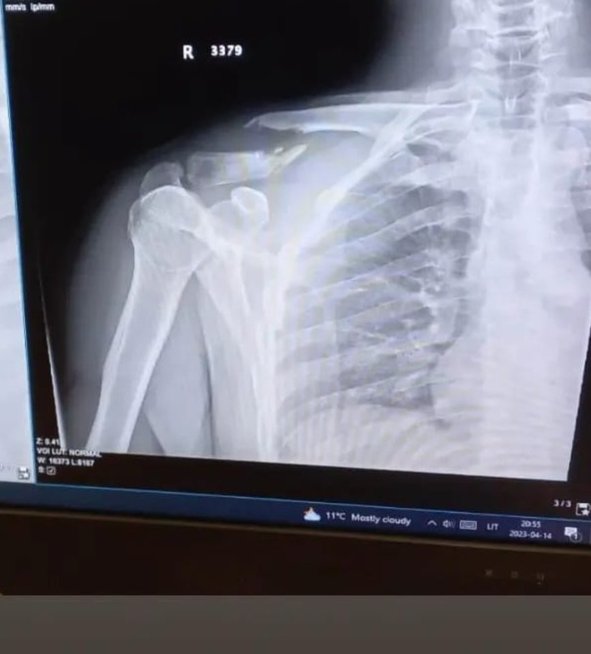

Nukentėjusysis iškart buvo pristatytas į Respublikinę Vilniaus universitetinę ligoninę, čia nustatytas raktikaulio lūžis. Tačiau vyras buvo gerokai nustebintas sužinojęs, kad su lūžusiu raktikauliu teks važiuoti namo.

„Atvykus padarė nuotrauką, matosi lūžis, bet jam tik uždėjo tvarstį, kad ranka per daug nejudėtų, išrašė vaistų nuo skausmo ir sakė, kad gal kitą savaitę išoperuos, jei bus vietų. Gal? Čia tikrai viskas normalu?“ – stebėjosi Indrė.

Paprašyta pakomentuoti situaciją Respublikinė Vilniaus universitetinė ligoninė nurodė, kad operacijų skubumą, esant kaulų lūžiams, lemia konkrečios klinikinės indikacijos.

„Nedelsiant atliekamos operacijos, kai patiriami atviri lūžiai, lūžus stambiesiems apatinės galūnės kaulams, stuburui ar esant politraumai – t. y. tokios, kurių neatlikus iš karto, vėliau gresia didelės komplikacijos ar net kyla grėsmė gyvybei. Tačiau yra lūžių, kurie chirurginės intervencijos gali laukti keletą dienų ar net iki kelių savaičių – taip gali būti esant uždariems, izoliuotiems, smulkių kaulų, dažniausiai viršutinių galūnių lūžiams. Tokių operacijų rezultatas nepriklauso nuo to, ar jos atliktos iš karto, ar vėliau. Kai kuriuos lūžius net ir rekomenduojama operuoti tik tada, kai jau bus atslūgęs patinimas“, – aiškinama ligoninės atsiųstame atsakyme.